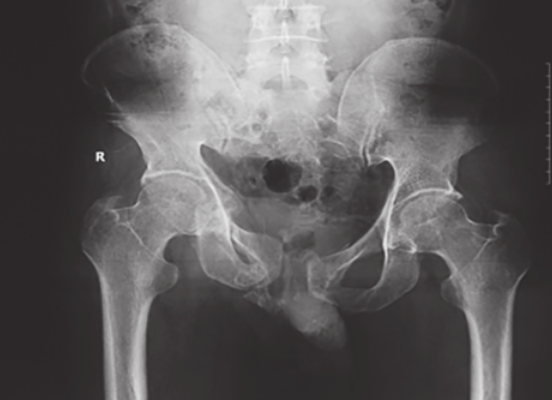

2、骨盆入口位X线检查:

可显示骶骨、髂骨后上部、骶髂关节上方、耻骨联合、耻骨支上缘及髋臼顶弓等。可用于鉴别骨盆环骨折的前后移位、旋转畸形、耻骨联合分离等(图2-3)。

图2骨盆入口位X线片1,可见左侧髂骨体骨质破裂,部分骨块分离,累及髂骨翼及骶髂关节面;左侧耻骨上、下支骨折,累及耻骨联合,提示骨盆前环损伤;双侧骶髂关节对位可,并未发生前后旋转移位

图3骨盆入口位X线片2,可见右侧骶骨翼骨折,耻骨联合分离,提示骨盆前后环损伤,右半侧骨盆向后移位